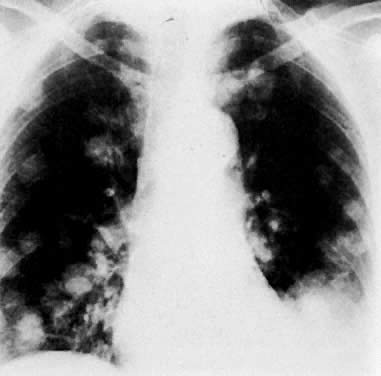

Multiple metastatic nodules in a patient with uterine leiomyosarcoma. Note pleural effusion in the left costophrenic angle.

Endometrial carcinoma metastatic to both lower lung fields (lower left and lower right arrow). There is also destruction of the eighth rib (middle arrow) and an extrapleural lesion (upper arrow) on the left.

Posteroanterior chest film in a patient with metastatic cervical carcinoma shows multiple cavitating metastatic lung lesions.